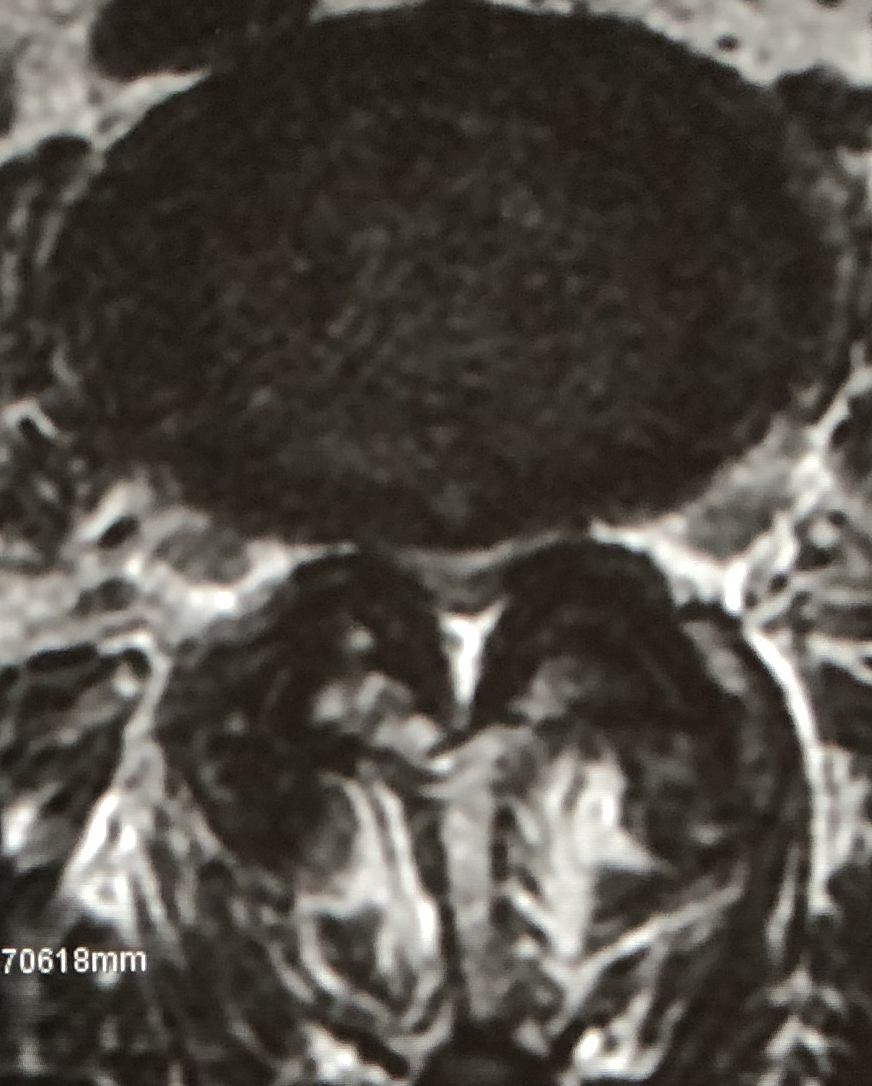

eXtreme Lateral Interbody Fusion(XLIF)は、主に左脇腹からの小皮切で腰椎に側方からアプローチし、脊椎前方に十分な骨移植を行ない脊椎の矯正固定を行なう手術方法です。脊柱管内には一切触れずにす椎間板の高さを増大させてすべりを矯正し、間接的な神経の除圧が可能です。

| 術前 | 術後 | |

| MRI |

|